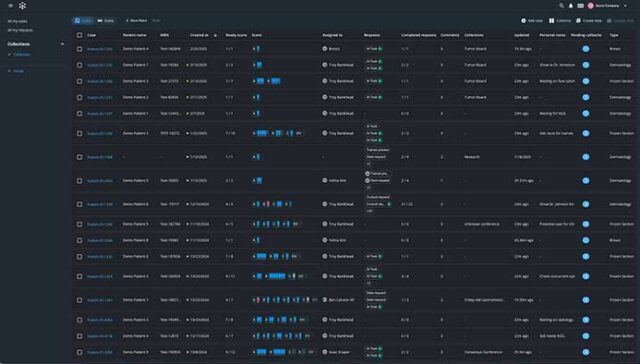

Built with pathologists to deliver an ultrafast cloud-based viewer, flexible worklist, integrated workflows, and state-of-the-art AI.

Techcyte Fusion: The unified anatomic and clinical pathology AI platform

What to expect from the Techcyte platform